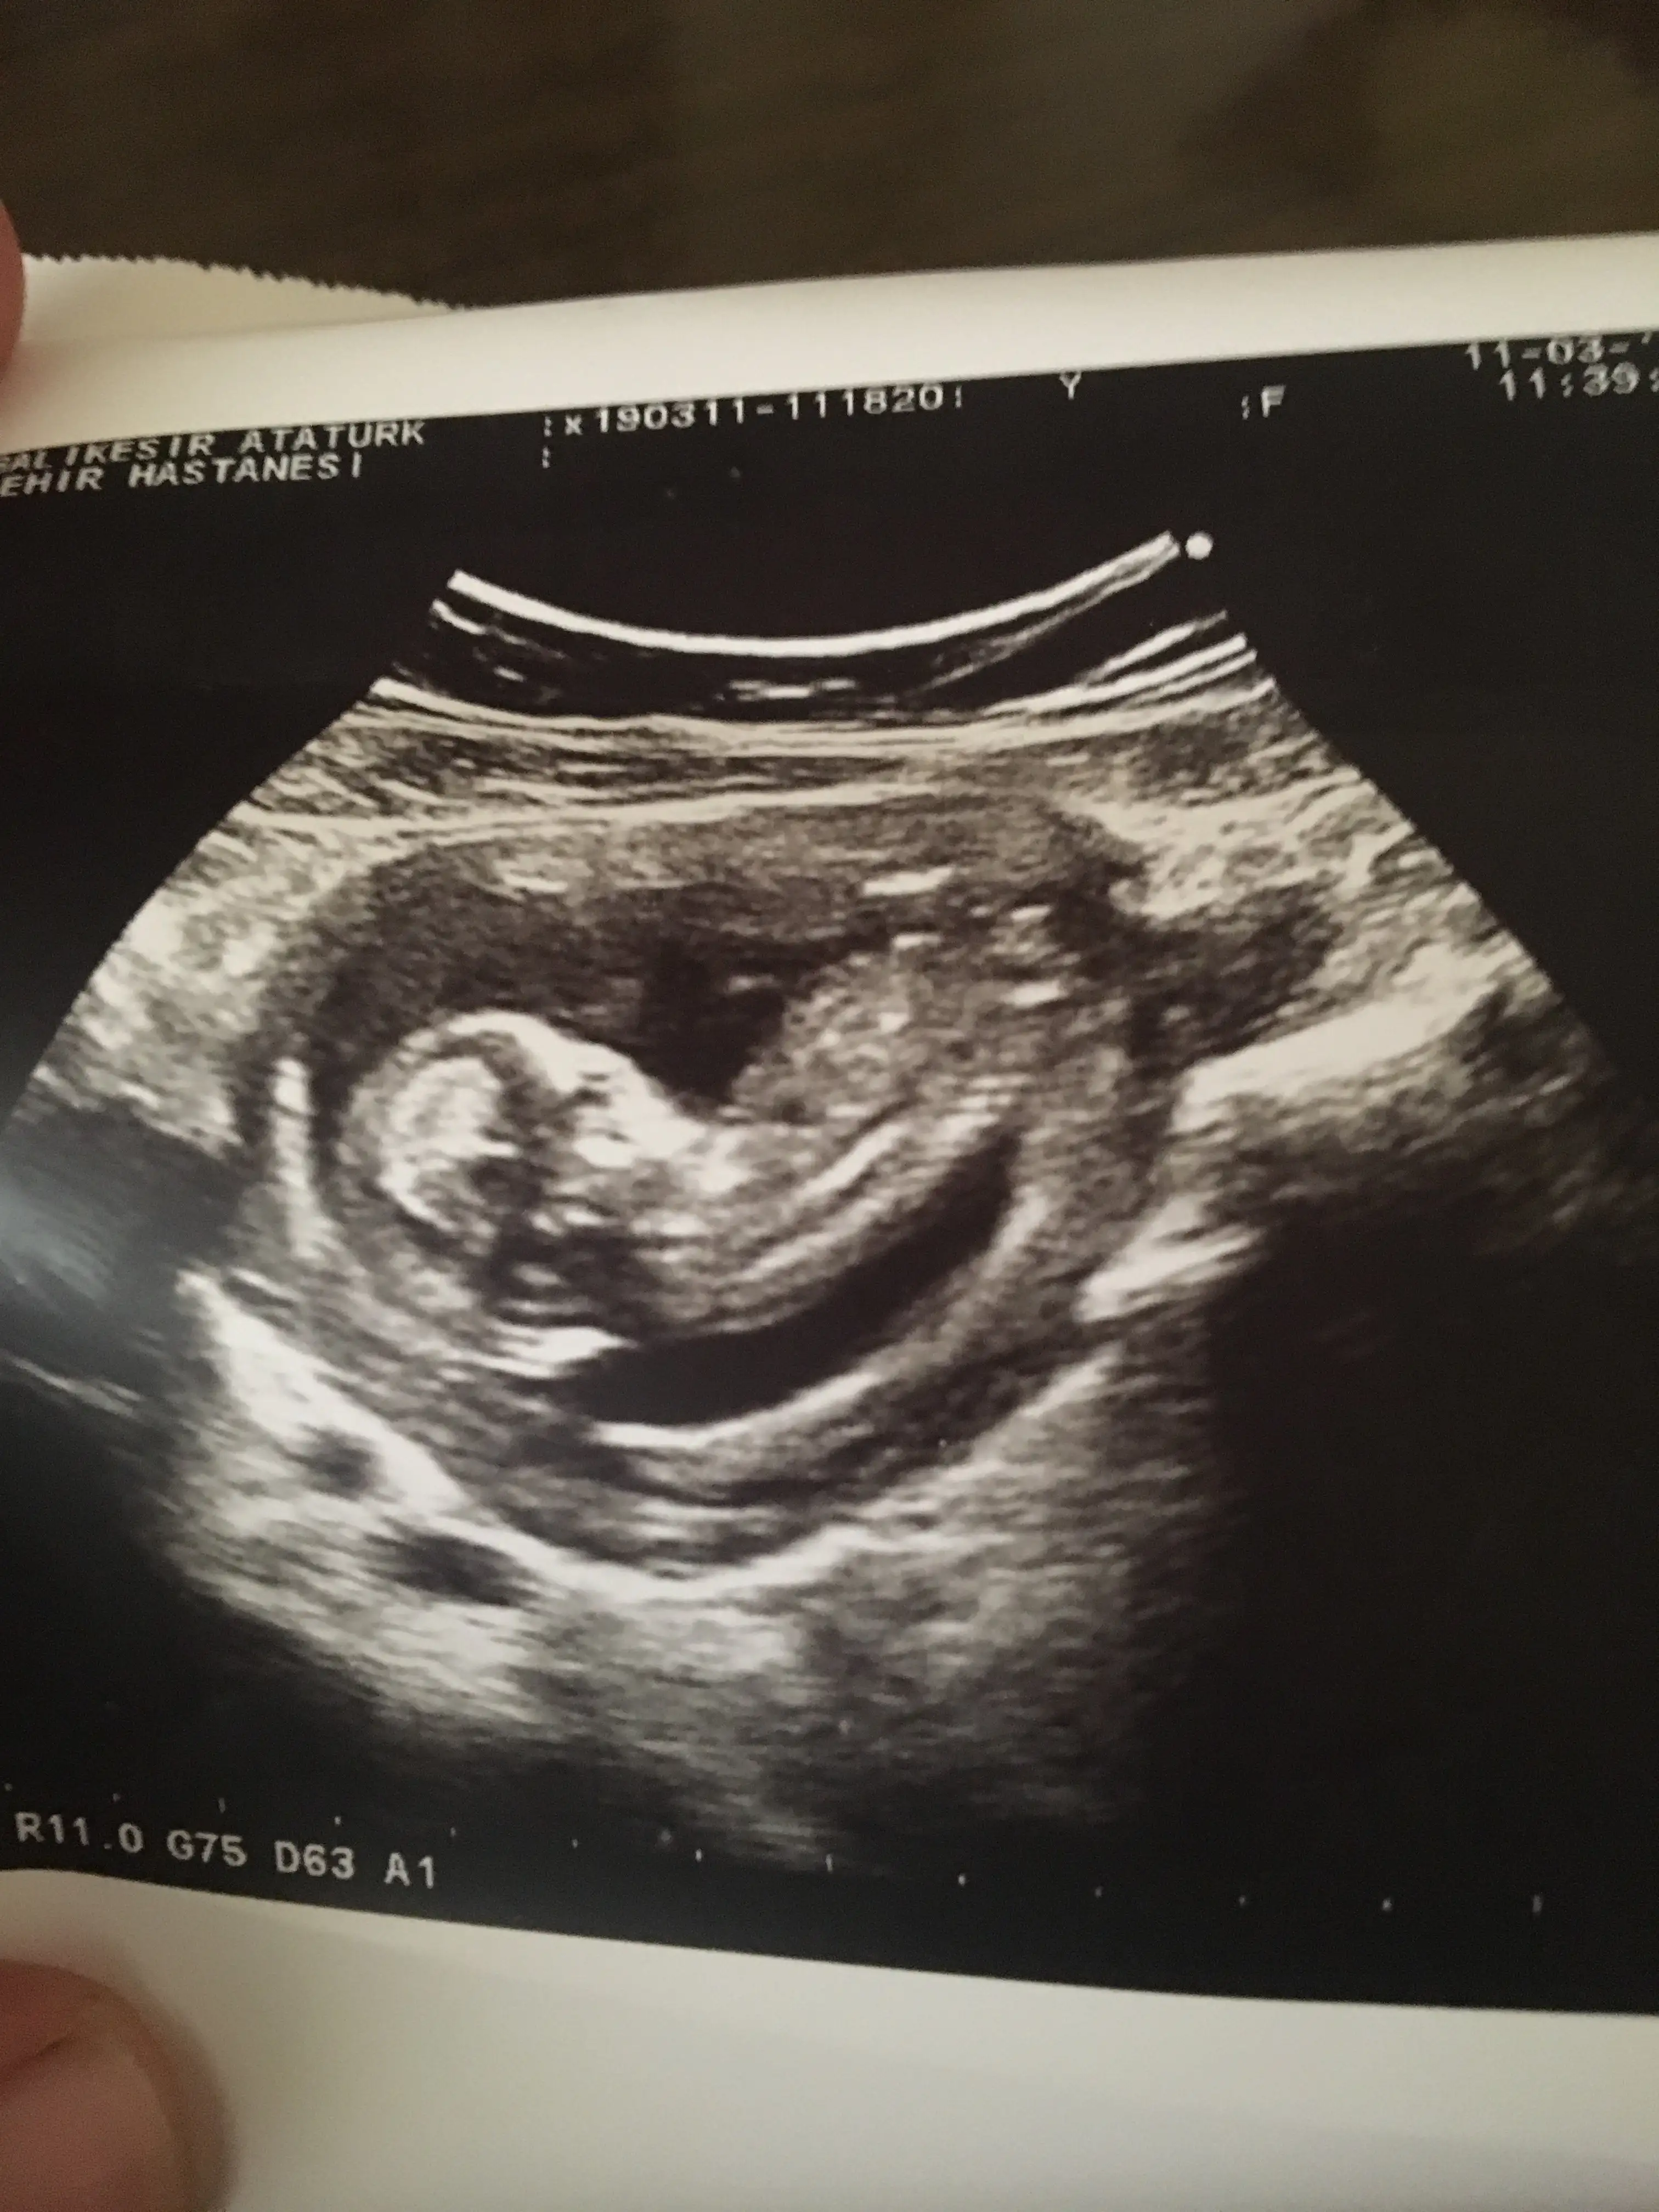

Merhaba canım bu 12 haftalık usg miz daha belli mi? Ya da fikri olan var mı

Kıza benzettim CanımArkadaşlar bana da yorum yapar mısınız lütfen 12 haftalık bebeğim